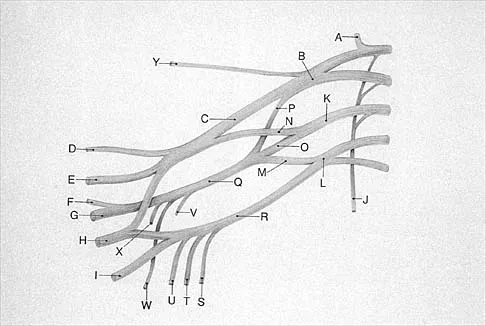

What structure is marked Q in the diagram of the brachial plexus shown in Figure 22?

Explanation